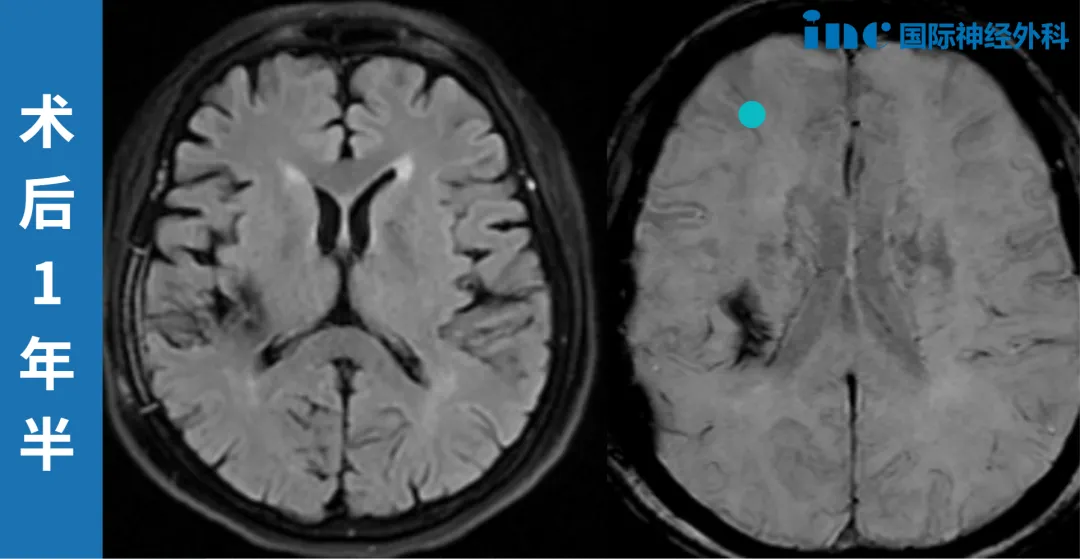

近日,INC国际神经外科的巴特朗菲教授为柯女士完成了术后2年的随访,巴教授的专业解读像一剂定心丸,让她在面对未来生活时更添了从容的底气。

此次随访中,柯女士提及自身症状变化:“舌头和右侧脸部的麻木感好多了,但双脚、右腿还有手术区域的麻木胀痛偶尔会出现。”同时,她还特别询问了核磁报告中“右侧额颞交界区斑片状低信号”的意义,这份细致恰是她对抗疾病的缩影。

面对她的这些困惑,INC神外的巴特朗菲教授给出了专业解答:“值得庆幸的是,对于当初那么大的出血病灶,通常病人会有更严重的问题,而您的症状非常轻微,这是极大的幸运。”

针对核磁显示的低信号,巴教授进一步解释,“这个病灶很小,并非缺血性改变,在您这个年龄段属于常见情况,甚至可能是正常生理表现,完全无需担心。更重要的是,海绵状血管瘤区域的恢复非常好,没有临床意义。”